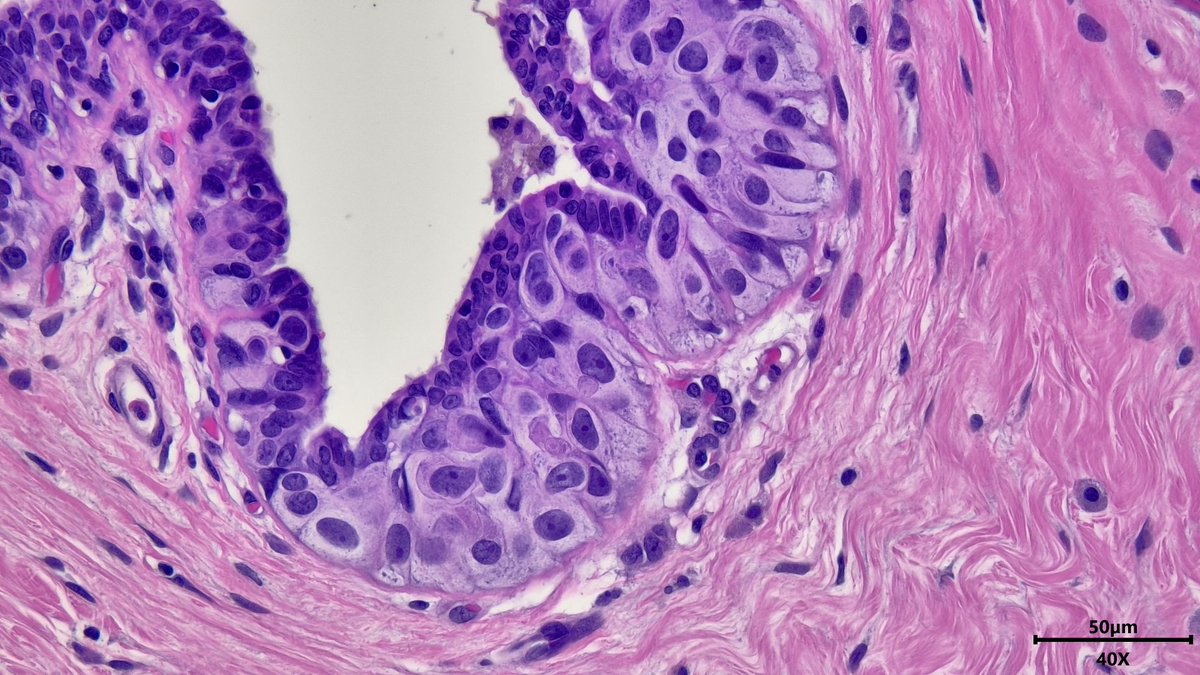

Happy Halloween #pathx and #PathTwitter ! 👻🎃Something wicked is lurking in this duct 🧌, pagetoid spread of DCIS #breastpath